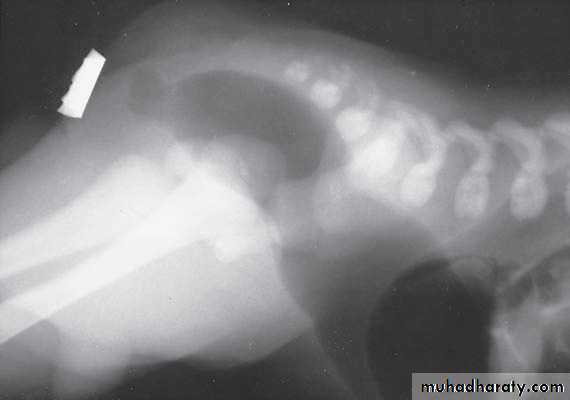

Scaphoid abdomen